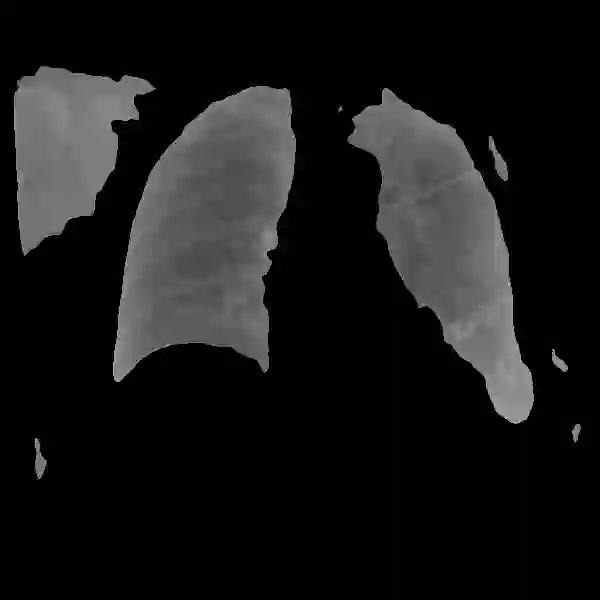

Deep learning technologies have already demonstrated a high potential to build diagnosis support systems from medical imaging data, such as Chest X-Ray images. However, the shortage of labeled data in the medical field represents one key obstacle to narrow down the performance gap with respect to applications in other image domains. In this work, we investigate the benefits of a curricular Self-Supervised Learning (SSL) pretraining scheme with respect to fully-supervised training regimes for pneumonia recognition on Chest X-Ray images of Covid-19 patients. We show that curricular SSL pretraining, which leverages unlabeled data, outperforms models trained from scratch, or pretrained on ImageNet, indicating the potential of performance gains by SSL pretraining on massive unlabeled datasets. Finally, we demonstrate that top-performing SSLpretrained models show a higher degree of attention in the lung regions, embodying models that may be more robust to possible external confounding factors in the training datasets, identified by previous works.